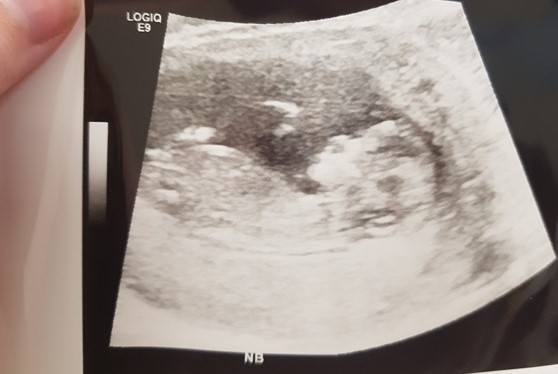

Hi! Please can I get some guesses for boy or girl based on either nub or skull theory please based on these pictures. :) I am 12+6 in these two photos. They are the only two I could get where there would be a possible nub.

I can't see a clear nub in either of these, sorry.

I would say girl from the first, in the other ones I can’t see a clear nub